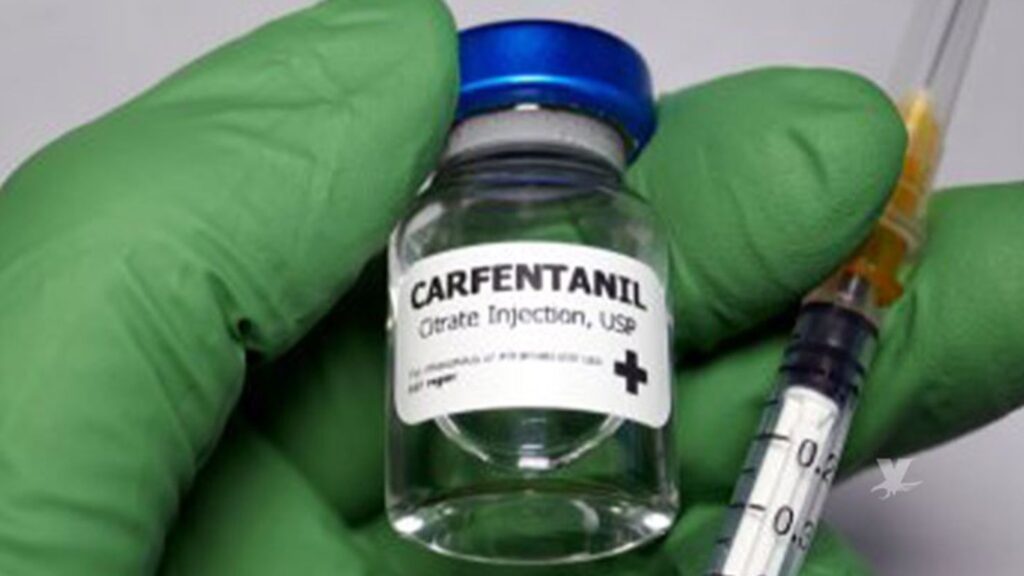

Alerta en EE.UU. por carfentanilo, opioide 100 veces más potente que el fentanilo

Originalmente diseñado como tranquilizante para grandes mamíferos —como elefantes—, el carfentanilo es 100 veces más fuerte que el fentanilo, y representa un riesgo letal incluso para personas con alta tolerancia a los opioides, advirtió la DEA en un comunicado. Washington, D.C. – La Administración para el Control de Drogas (DEA) emitió una alerta urgente tras […]